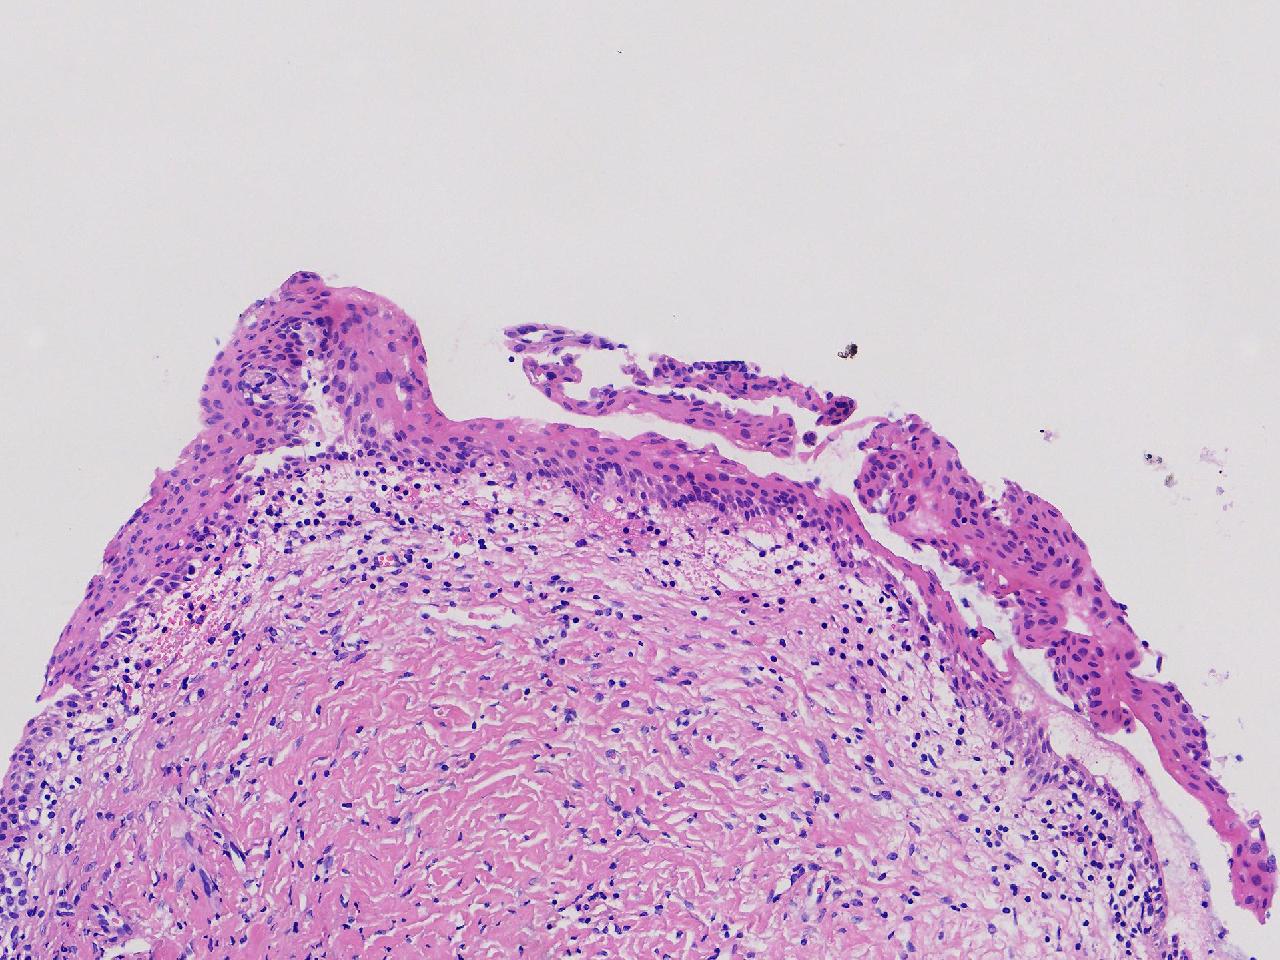

萎缩性? CIN1级?

女,64岁,宫颈活检,HPV不详。

宫颈活检

慢性宫颈炎

萎缩